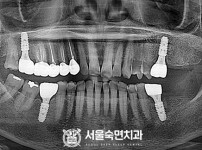

임플란트-전후사진4